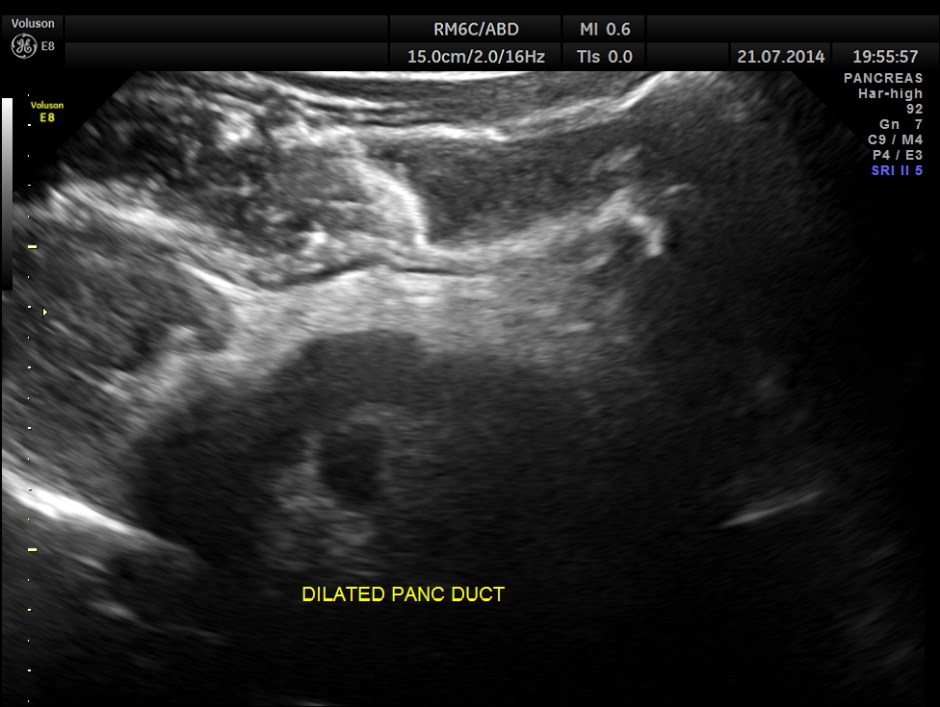

The following pictures show the pancreas.

Pancreatic duct is dilated prominently.

Pancreatic duct dilated.- 12.9 mms.

Pancreatic calculi are seen.